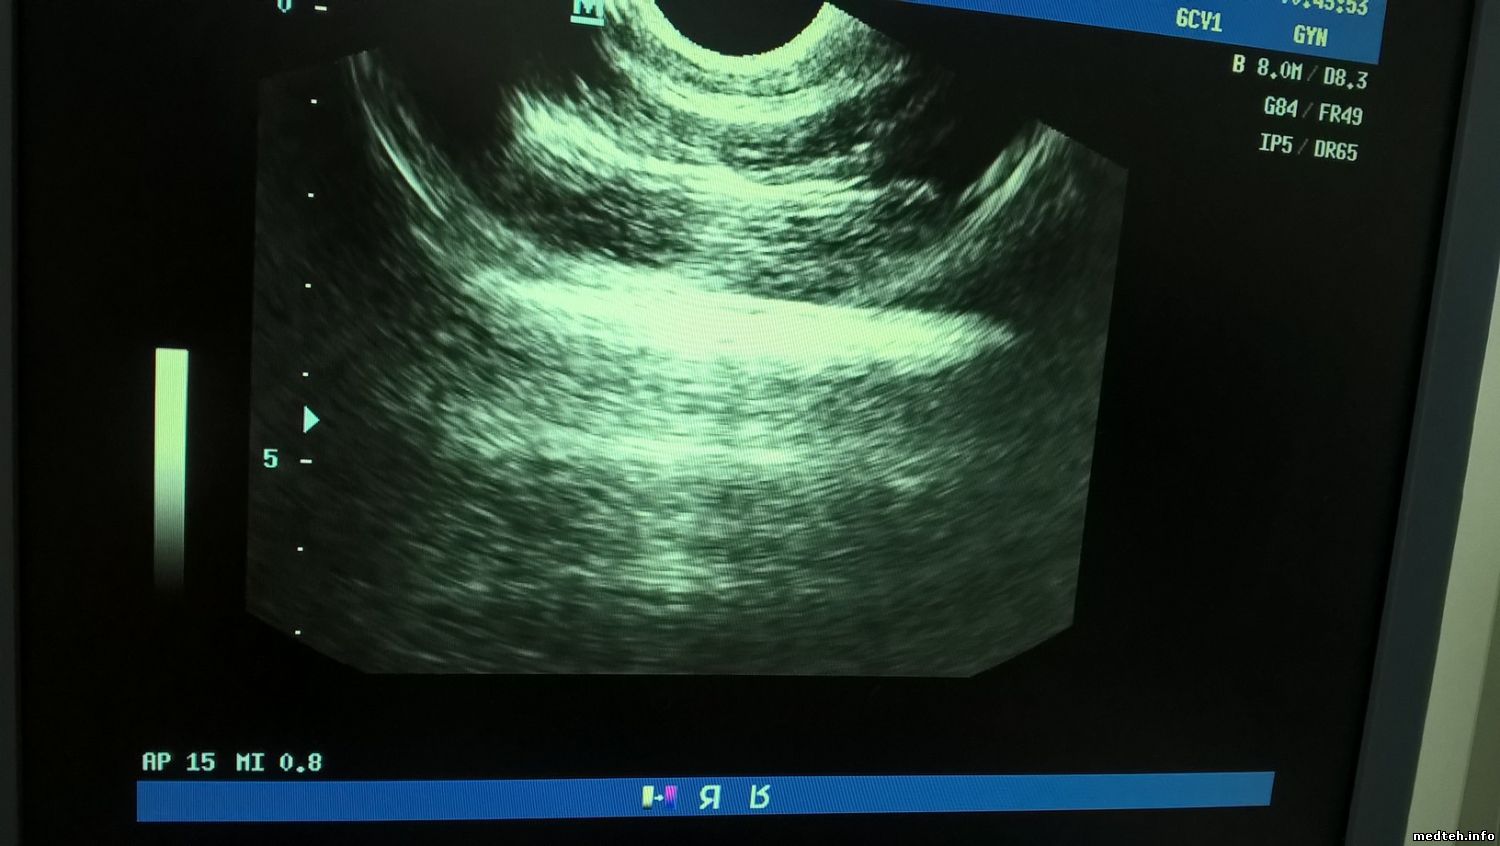

Помогите разобраться в следующей проблеме. Есть два Mindray DC6 и один вагинальный датчик. С год назад врачи забраковали один аппарат по причине помех на изображений. Фото 9363159 и 5455816. Решили проверить датчик и подключили к другому аппарату. Сначала изображение их устраивало, а месяца два назад начали жаловаться опять. Фото 5410773 и 6255828. Решили отдать датчик на проверку специалистам. Их заключение - датчик рабочий. На линейном и конвексном датчиках эти помехи присутствуют тоже, но они не так выражены. Если отключить от аппарата probe board - помехи остаются, если отключить transmission board - помех нет, но можно сказать, что нет сигнала - нет помех. Посоветуйте, что можно сделать с этой неисправностью. Буду признателен, если кто-нибудь пришлет фото картинки с такого же аппарата и датчика, чтобы сравнить.

5410773.jpg (134.1 Kb) · 6255828.jpg (100.2 Kb) · 9363159.jpg (107.4 Kb) · 5455816.jpg (126.0 Kb)